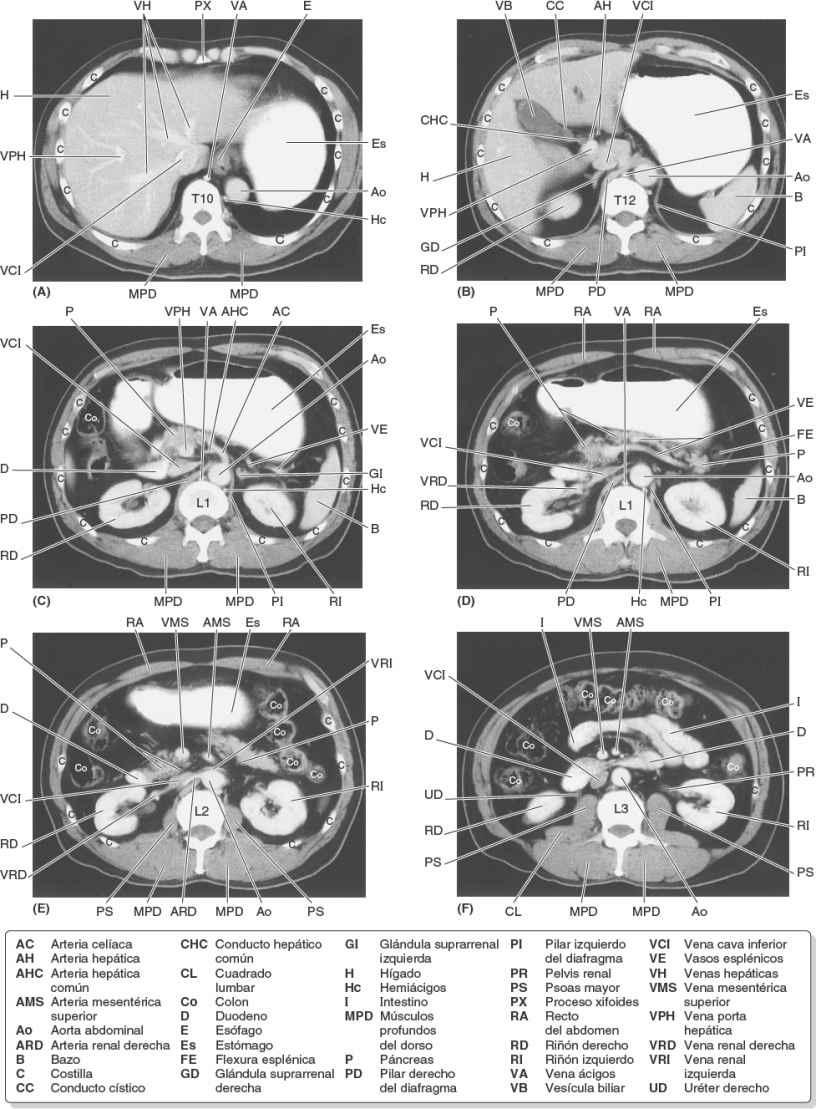

Fig. 5-103. A a F) Imágenes de TC transversa (axial) del abdomen en niveles progresivamente inferiores que muestran la pared abdominal, las vísceras y los vasos sanguíneos.